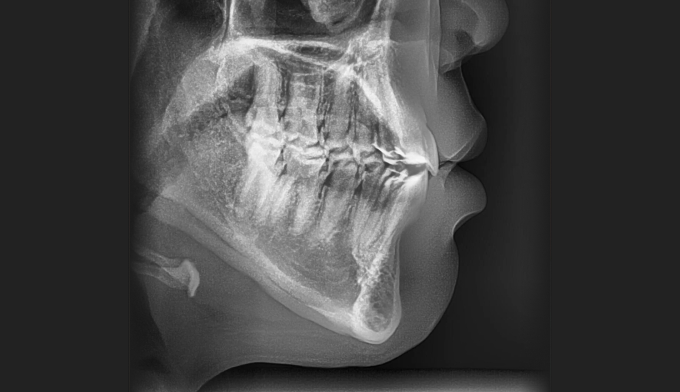

개방교합은 좋지않은 발음을 만들기도 하지만 심미적으로도 좋아보이지 않아서 교정치료를 받으러 많이 오십니다. 치아는 가지런하므로 교정치료가 어렵지 않아 보이지만 개방교합의 치료는 교정용 미니스크류의 식립도 필요하며, 재발도 잘되는 어려운 교정입니다. 교정치료 이후에 재발되지 않게 주기적인 관리 및 연습도 필요합니다.

어금니의 미니스크류의 식립을 통하여 개방교합을 치료하였습니다. 총 치료기간은 13개월입니다.